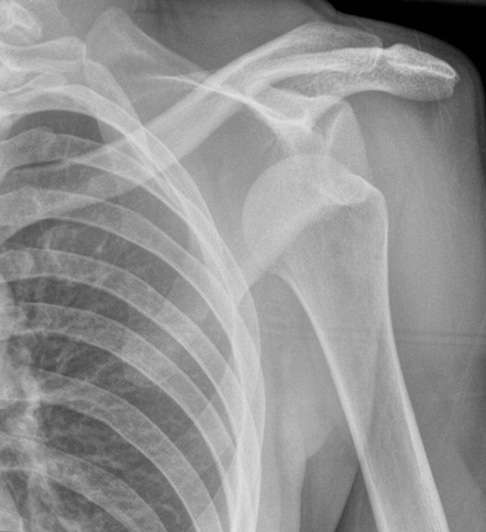

Die orthopädische Untersuchung gibt Hinweise auf das Vorhandensein, das Ausmaß und die Richtung der Instabilität im Schultergelenk. Mittels Röntgenbild kann der Arzt knöcherne Verletzungen am Oberarmkopf und an der Gelenkpfanne diagnostizieren oder ausschließen. Um die Schädigung von Gelenkkapsel und Bändern zu erkennen, ist in vielen Fällen eine Kernspintomographie (MRT) der Schulter erforderlich. Hier lassen sich Verletzungen der Gelenkkapsel, der Sehnen und der Gelenklippe (Labrum) erkennen. Auch eine Untersuchung der Muskeln und Sehnen mittels Ultraschall kann zur Diagnose beitragen. Anhand der Ergebnisse der Untersuchungen legt der Orthopäde das operative Vorgehen fest.